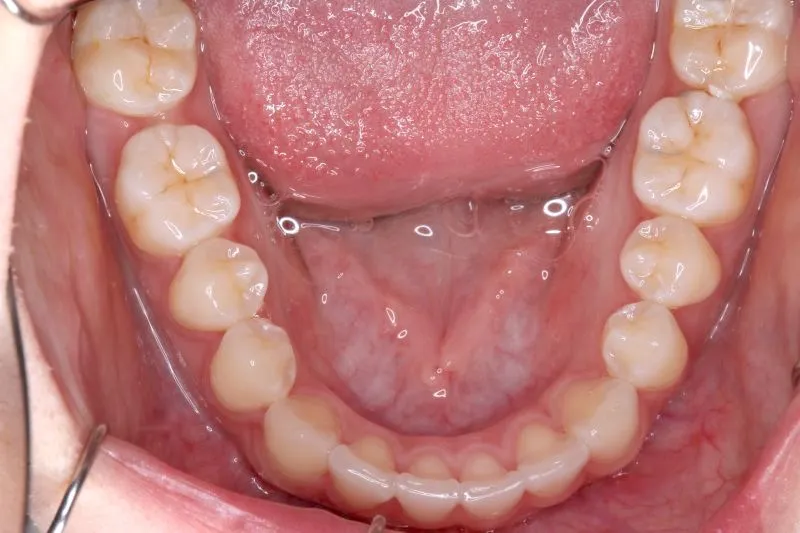

初診時年齢 小学校6年生 (女性) 主訴 犬歯がずれている・噛み合わない

診断名 叢生・交叉咬合 装置名

右下の犬歯がずれて生え噛み合わせの邪魔をしています。

歯は抜かず、上下マルチブラケット装置を使用し治療いたしました。

治療回数54回、9年3ヶ月の治療期間で矯正治療を終了しました。